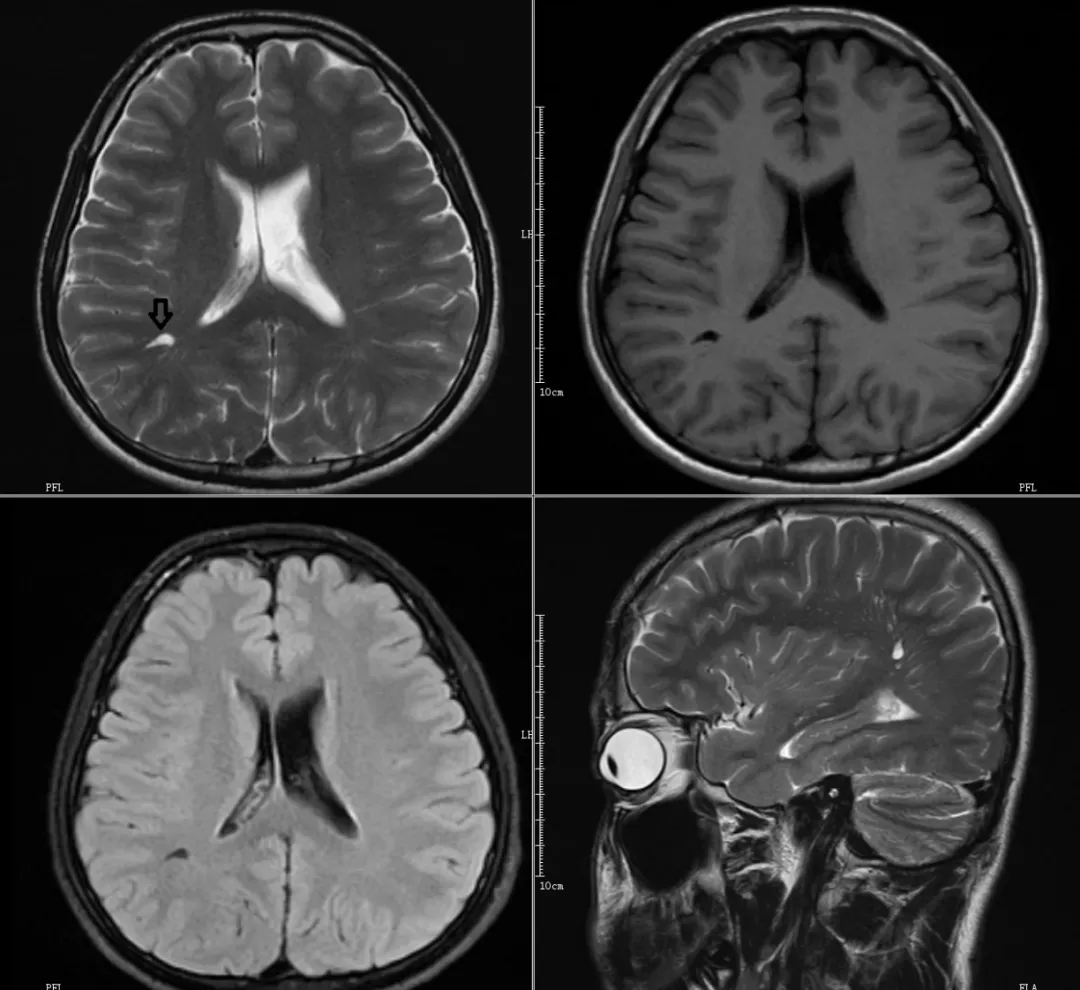

CASE1

右侧脑室旁V-R间隙

CASE2

双侧额叶白质内V-R间隙(Ⅱ型)